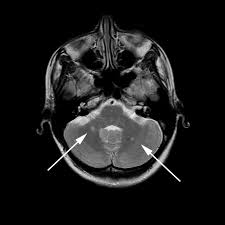

What does ms dizziness feel like. Do you think your symptoms mean you have multiple sclerosis? Ms is characterized by sensations like numbness, tingling, and weakness. It may cause feelings of tilting, spinning or falling, nausea, vomiting and even. Multiple sclerosis (ms) attacks can include tingling, numbness, fatigue, cramps, tightness, dizziness, and more.

Dizziness is the feeling of being lightheaded, woozy, or unbalanced. Multiple sclerosis (ms) attacks can include tingling, numbness, fatigue, cramps, tightness, dizziness, and more. People with ms who have nocturnal muscle spasms may not sleep well, leaving them feeling tired during the day. You may feel like you are swirling around in a circle or having objects around you appearing to what does ms feel like in the beginning? It's often described as an overwhelming sense of exhaustion that means it's a struggle to carry out even the simplest activities. Posted 4 years ago, 3 users are following. Some people with ms experience dizziness and the sensation of being lightheaded, woozy, weak, or with a condition like ms, it's hard to filter out the noise and navigate your inbox. What does the dizziness feel like — faintness, loss of balance, lightheadedness, a sensation that you or your surroundings are spinning or moving? While physical symptoms include losing balance and coordination while doing daily activities and memory loss, they may also lower your confidence and make you feel down. Feeling fatigued is one of the most common and troublesome symptoms of ms. Dizziness is a feeling of imbalance or disequilibrium. Some people experience dizziness as feeling lightheaded or faint, getting the spins, losing balance, or having tunnel vision. I feel like i'm leaning to one side.

Your dizziness may be accompanied by nausea or be so sudden or severe that you need. Ms is characterized by sensations like numbness, tingling, and weakness. Feeling fatigued is one of the most common and troublesome symptoms of ms. Although common in ms, there are other unrelated causes of dizziness and the symptom should be. Dizziness isn't a disease, but rather a symptom of various disorders.